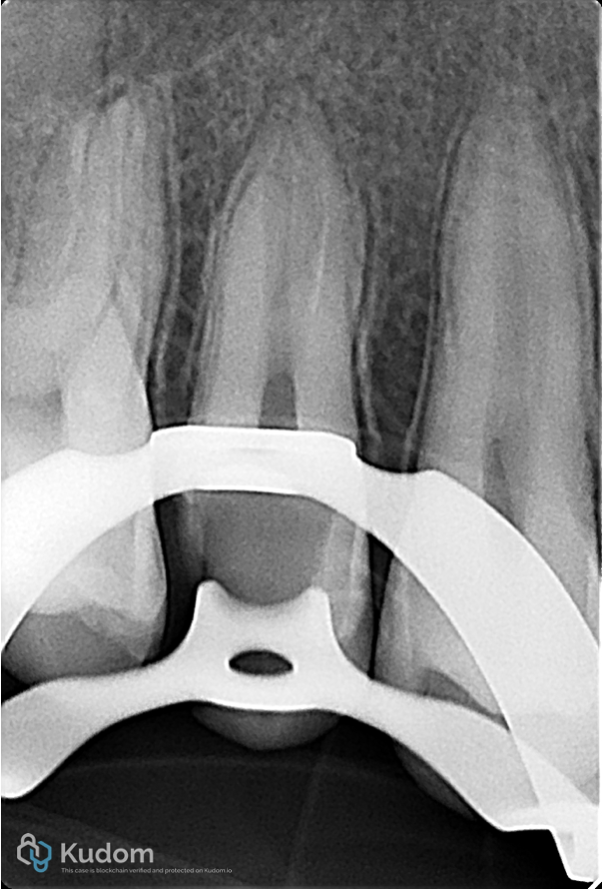

Fig. 26

Post-op Xray